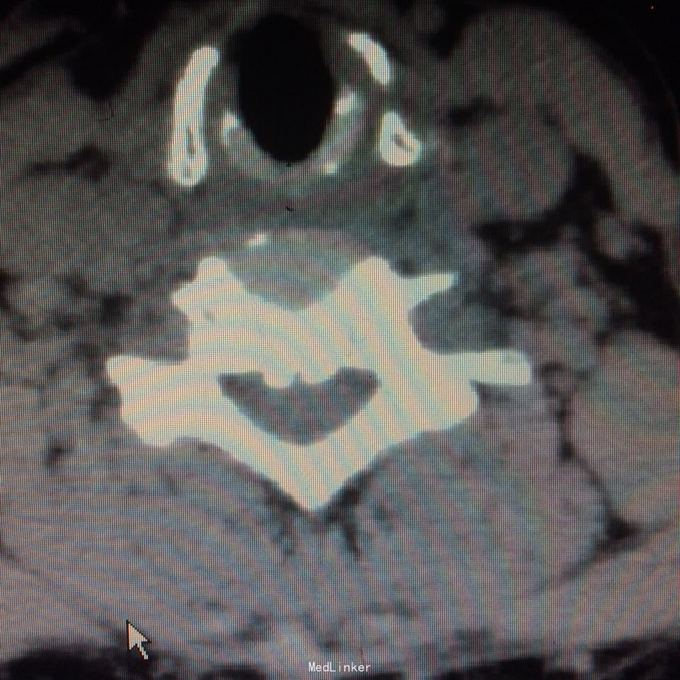

压头及右侧臂丛牵拉试验阳性,无明显浅感觉减退,右上肢肱三头肌肌力2级,双上肢腱反射活跃,双上肢病理征阳性 颈椎ct见颈椎6、7水平后纵韧带骨化,继发相应的椎管水平狭窄,自带核磁见颈椎2-7间盘向后突出,硬膜囊前缘受压